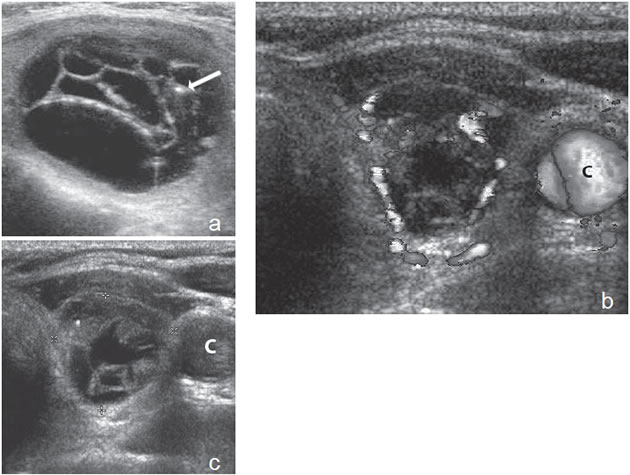

Un nódulo que tiene un componente quístico significativo, usualmente es un nódulo benigno hiperplástico, que ha acumulado abundante coloide (Figura 2a) o bien, un nódulo sólido que ha experimentado un proceso de degeneración colicuativa o hemorragia (Figura 2b). El coloide o el contenido líquido de un nódulo se ve anecogénico (negro en la imagen ecográfica) y las estructuras sólidas se ven ecogénicas (distintos tonos de grises), siendo la ecogenicidad similar al del parénquima tiroideo. En un nódulo sólido la ecoestructura y la ecogenicidad pueden ser variables. En general, la frecuencia de carcinoma es muy baja en nódulos quísticos13 y la mayoría de los carcinomas se presentan como nódulos sólidos (Figura 2c).

Figura 2. a) Quiste coloideo anecogénico y focos ecogénicos (flecha) con artefacto en cola de cometa; b) Nódulo mixto sólido-quístico (cabezas de flechas). Imagen vegetante (flecha) adherida a un tabique que se proyecta al lumen; c) Comparación entre el aspecto ecográfico de un cáncer papilar sólido (flecha abierta) y un quiste coloideo anecogénico.